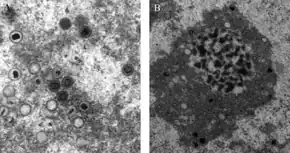

| Transmission electron microscope (TEM) image of cytomegalovirus (CMV) virions that were present in a (unknown) tissue sample. | |